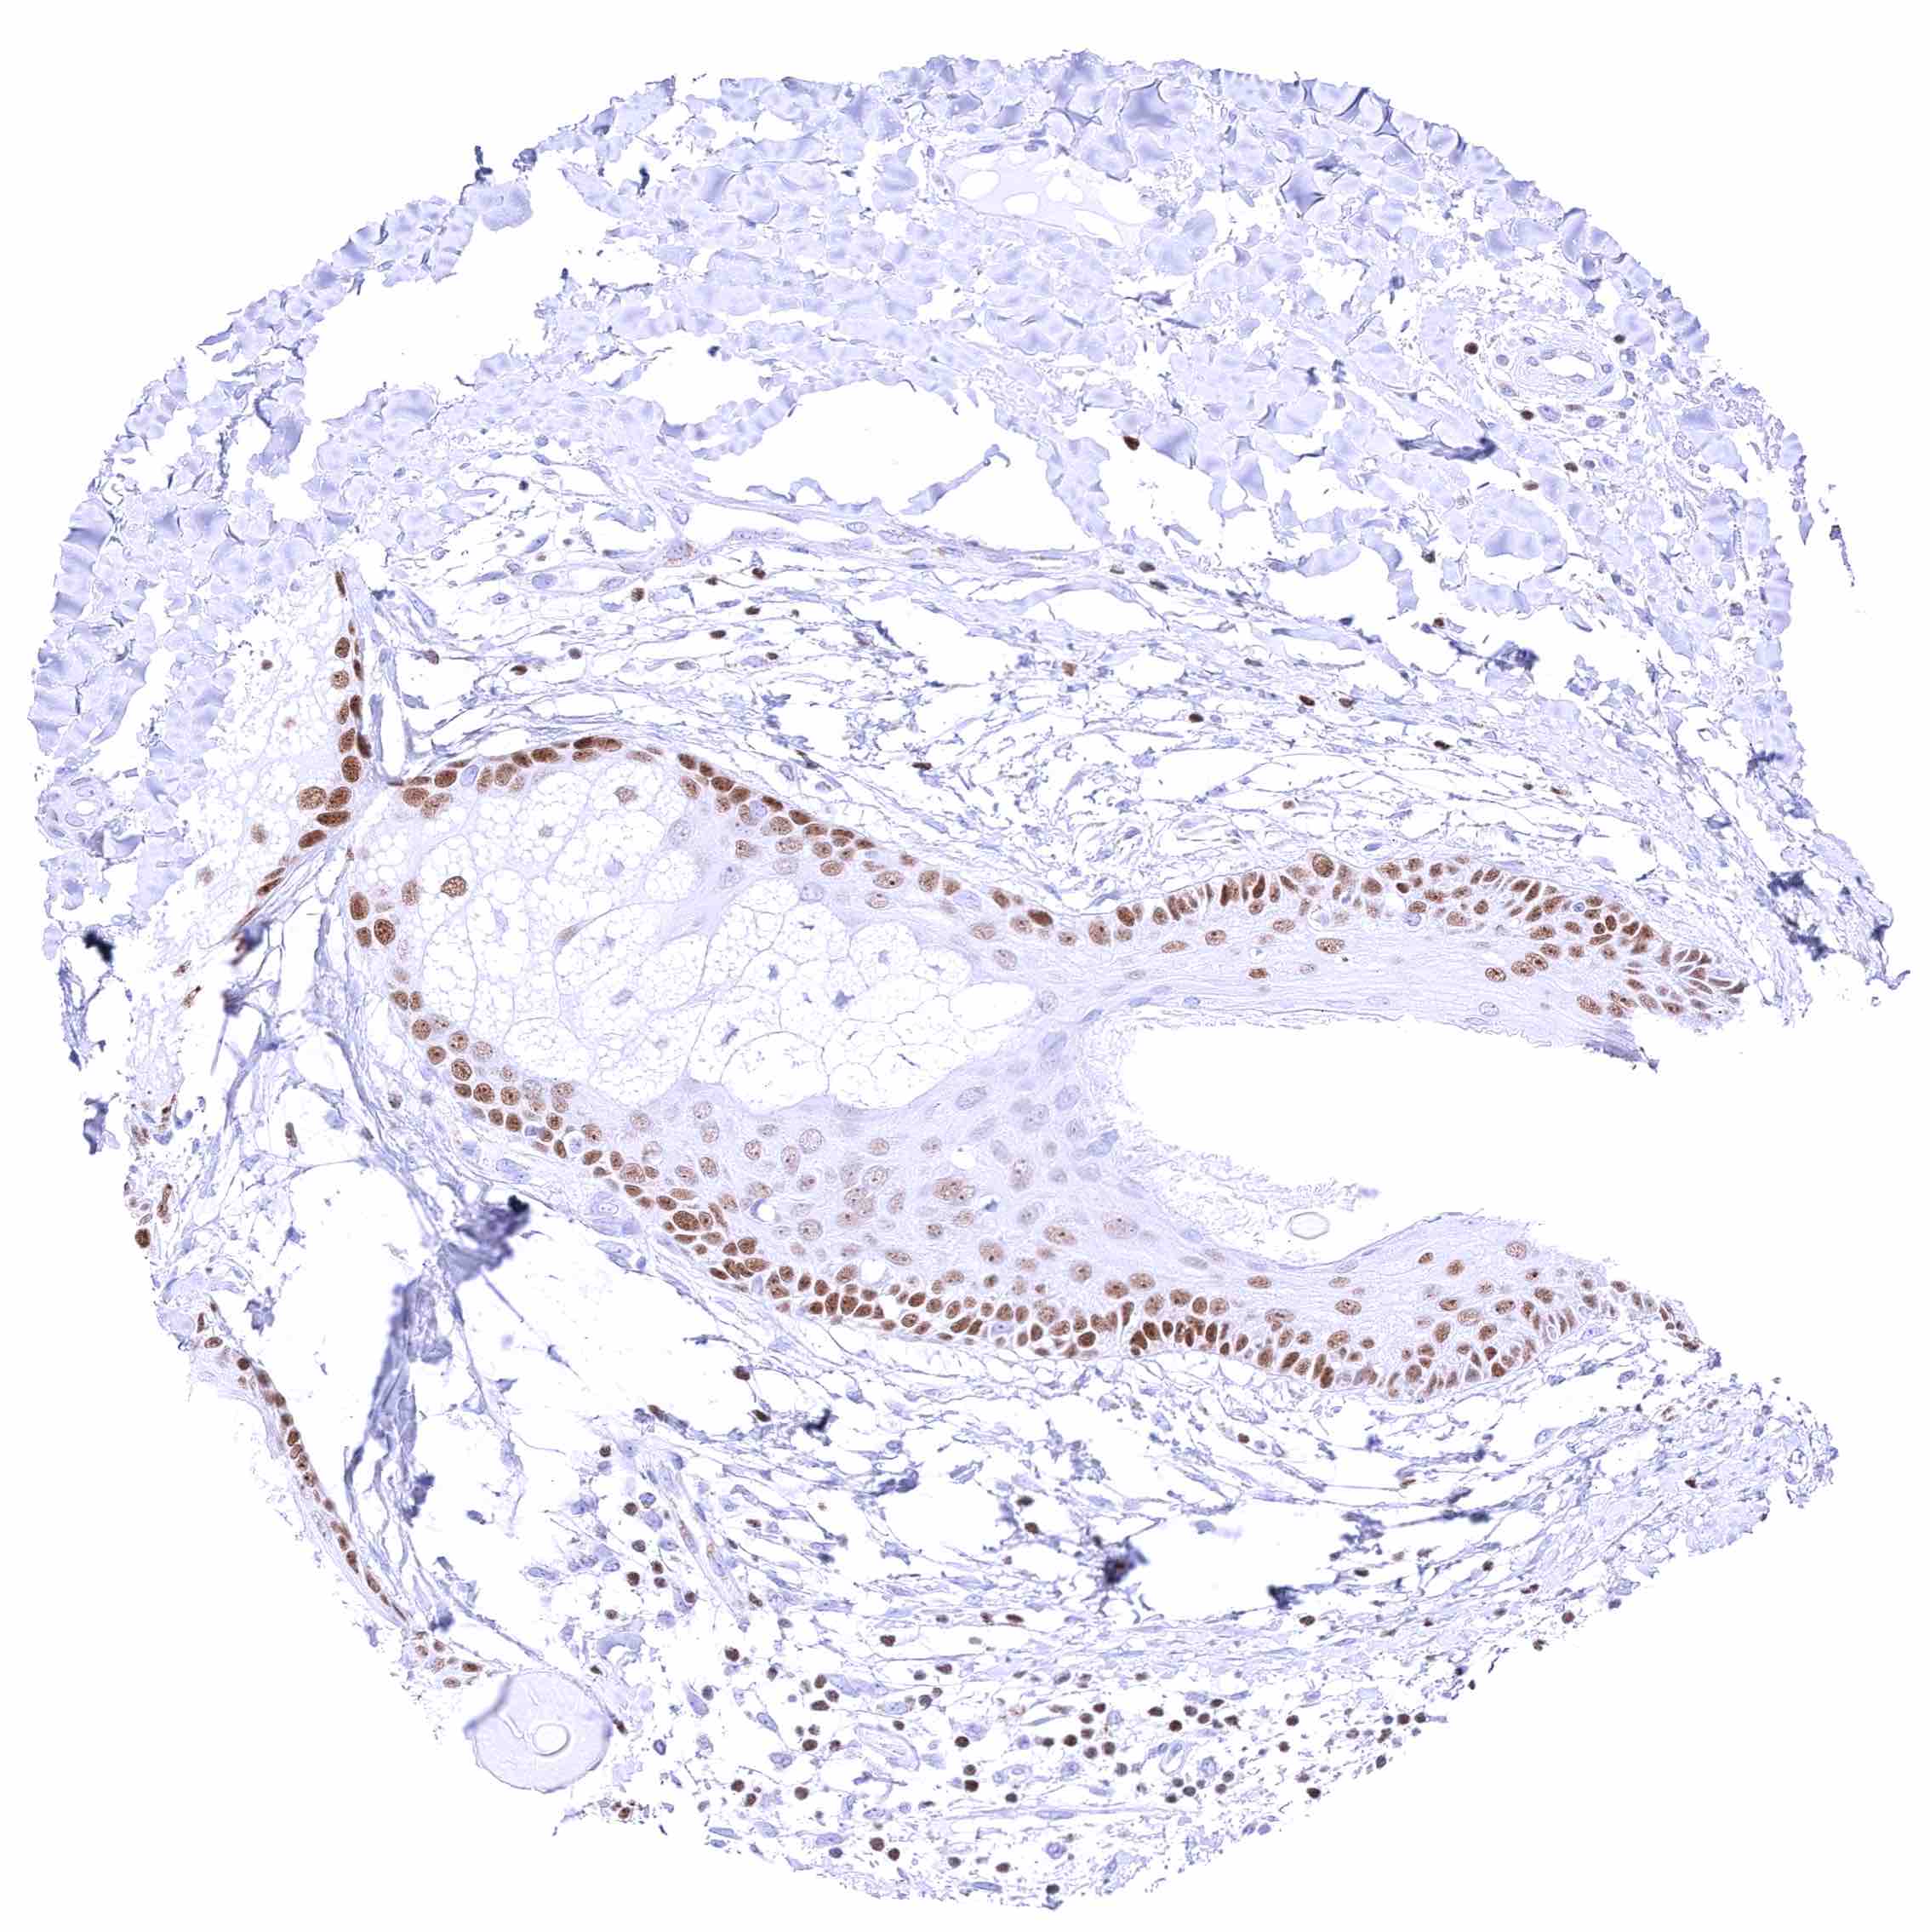

Placenta (amnion and chorion) – Strong nuclear GATA3 staining of chorion cells while amnion cells only show weak positivity.

Placenta, early – Strong nuclear GATA3 positivity of trophoblastic cells.

Placenta, mature – Strong nuclear GATA3 positivity of trophoblastic cells.